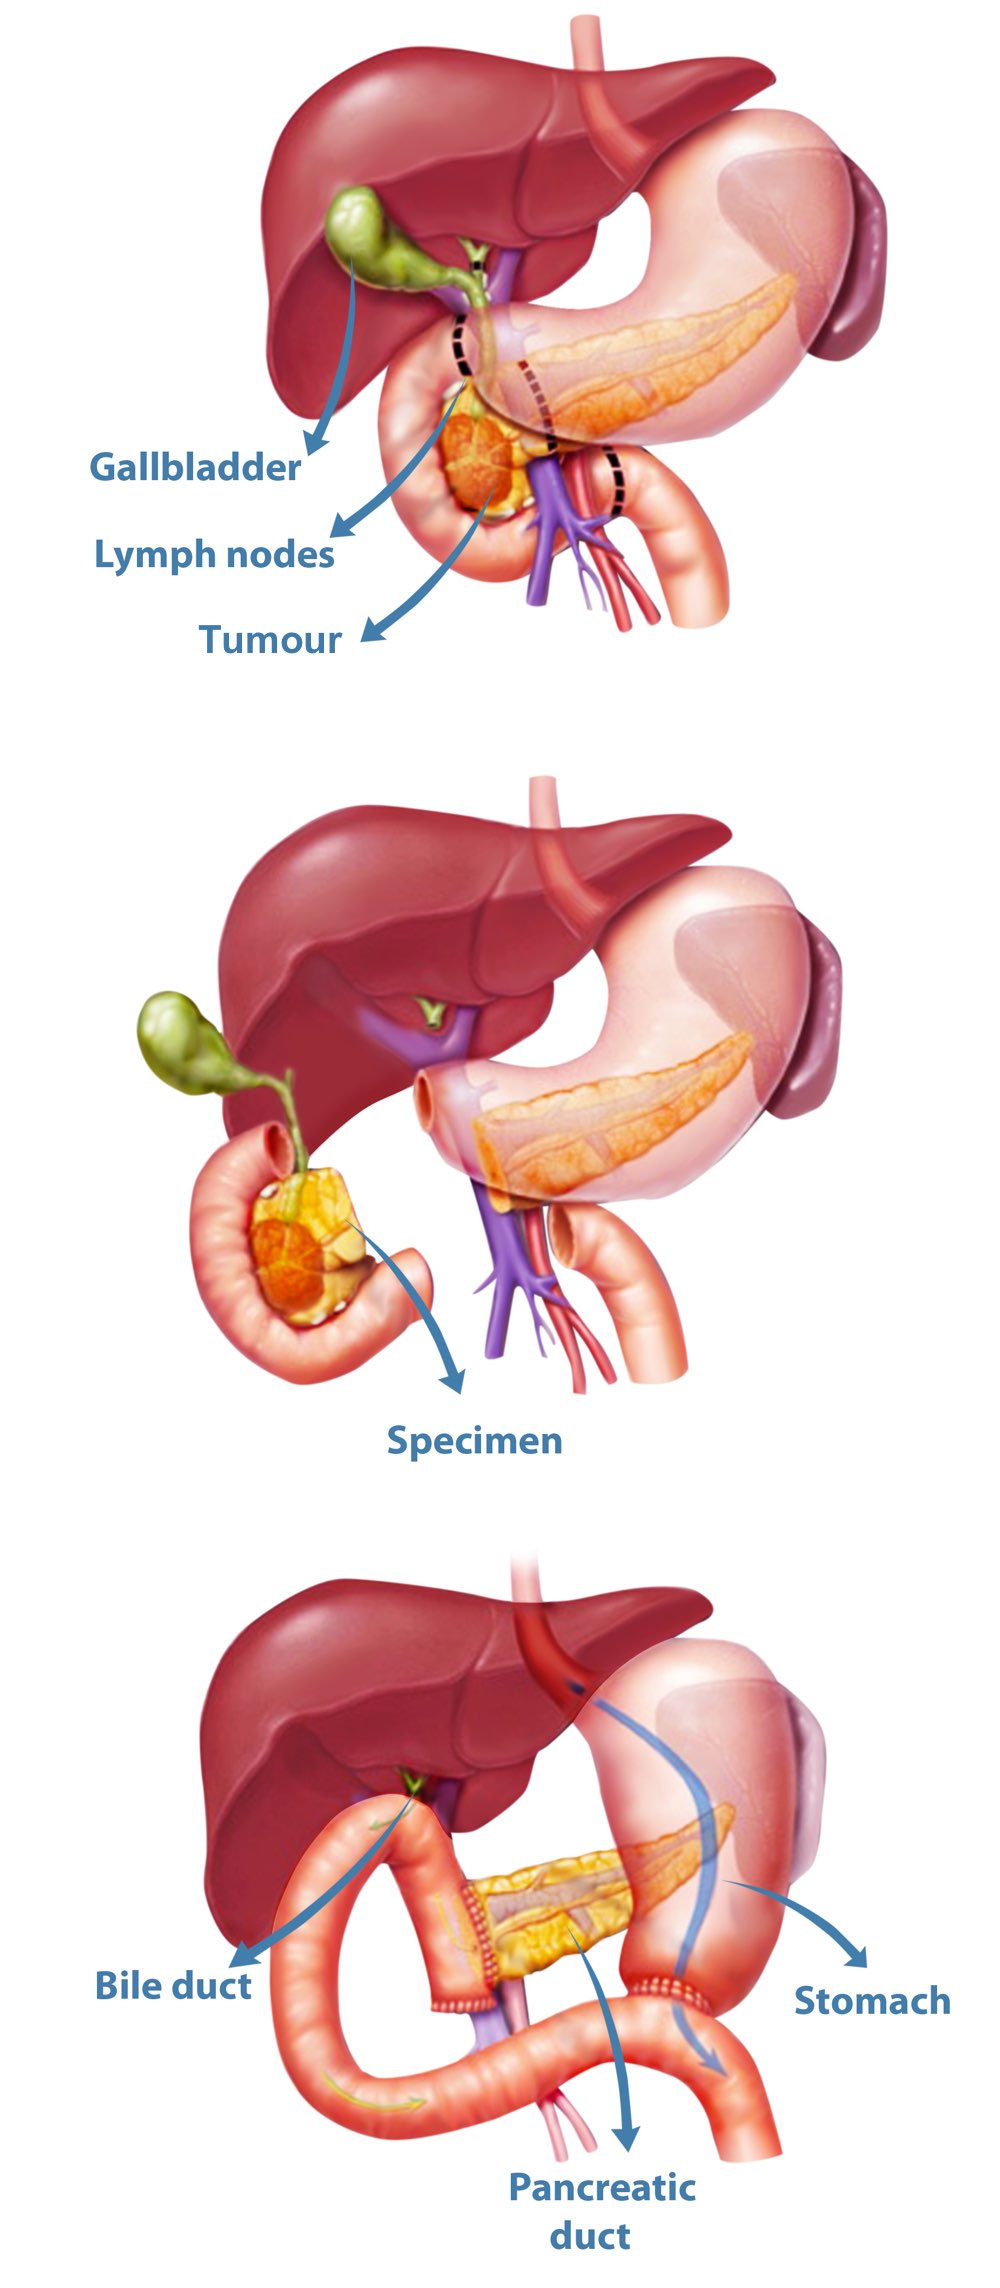

Фотографии медицинских исследований инсулиномы и синдрома Триады Уиппла